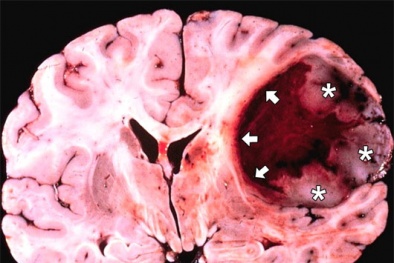

Hai loại protein gây ung thư não

(VietQ.vn) - Các nhà khoa học đã tìm ra hai protein được cho là nguyên nhân tạo ra các khối u ở não, các protein nói trên có khả năng kích thích và phát triển glioblastoma, một trong những loại u não ác tính phổ biến nhất.